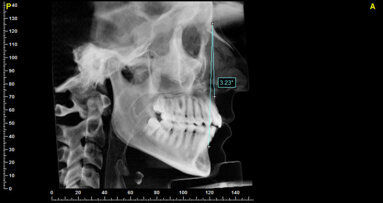

La paziente si presenta all’attenzione dello studio riferendo fastidi nella zona superiore sx, e all’anamnesi risultano trascorsi 3 anni dall’ultimo appuntamento di igiene presso altro centro. L’esame visivo e fotografico (Fig. 1) evidenziano un’alterazione dello stato dei tessuti perimplantari con sanguinamento spontaneo e lassità del tessuto molle, pertanto segue acquisizione di rx endorale da parte dell’odontoiatra (Fig. 2) da cui risulta un’importante riassorbimento osseo a carico dell’impianto. Segue un sondaggio perimplantare profondo (Fig 3), eseguito previa anestesia topica con Lidocaina 15%, per definire estensione e conformazione del difetto associandolo alla valutazione radiografica per la conta delle spire esposte.

Fig. 2